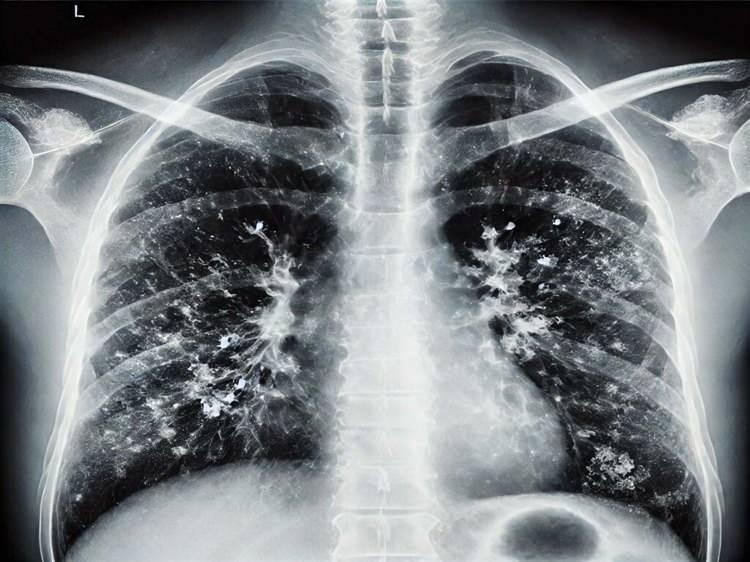

Prof. Dr. Şener 'süperenfeksiyon' için uyardı: ‘Dikkat etmek lazım, ücretsiz aşınızı olun

Zatürre, pnömoni, akciğer iltihabı gibi durumlar hastaneye yatışa hatta oksijen desteği ihtiyacına sebep olabilecek klinik tablolara yol açabiliyor. Bu açıdan dikkat etmek lazım. Aile hekimine başvurduğunuzda ücretsiz grip aşınızı olabilirsiniz" dedi.